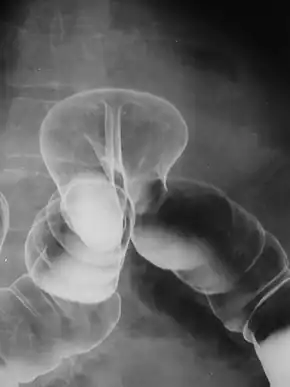

In the diagnosis of abdominal hernias, imaging is the principal means of detecting internal diaphragmatic and other nonpalpable or unsuspected hernias. Multidetector CT (MDCT) can show with precision the anatomic site of the hernia sac, the contents of the sac, and any complications. MDCT also offers clear detail of the abdominal wall allowing wall hernias to be identified accurately.[19]

By far the most common hernias (up to 75% of all abdominal hernias) are inguinal hernias, which are further divided into the more common indirect inguinal hernia (2/3, depicted here), in which the inguinal canal is entered via a congenital weakness at its entrance (the internal inguinal ring), and the direct inguinal hernia type (1/3), where the hernia contents push through a weak spot in the back wall of the inguinal canal. An indirect inguinal hernia and a direct inguinal hernia can be distinguished by their positioning in relation to the inferior epigastric vessels. An indirect hernia is situated laterally to these vessels, whereas a direct hernia is positioned medially to them. Inguinal hernias are the most common type of hernia in both men and women. In some selected cases, they may require surgery.